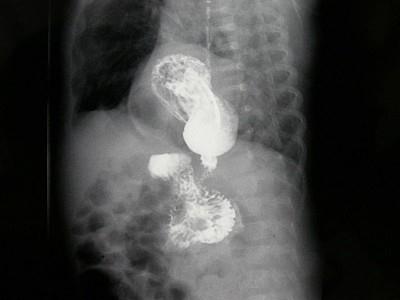

女,1岁,反复呕吐伴中度营养不良,结合影像,最可能的诊断为?(?)A.肺脓疡B.膈疝C.食道裂孔疝D.包裹性液气胸E.胃扭转

问题 女,1岁,反复呕吐伴中度营养不良,结合影像,最可能的诊断为?(?)

选项 A.肺脓疡 B.膈疝 C.食道裂孔疝 D.包裹性液气胸 E.胃扭转

答案 C